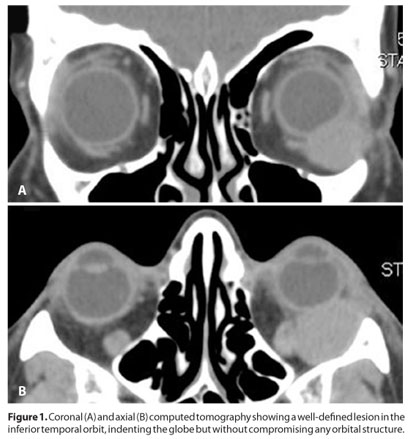

A 53 year-old woman presented with a slowly progressive, painless proptosis OS. During clinical examination, an upward displacement of the left globe was seen, although the exam was otherwise unremarkable. Visual acuity was 20/20 in both eyes and intraocular pressure was 16/16 mmHg. Computed tomography disclosed a round, homogeneous, well-delimited lesion in the inferior-temporal orbit, indenting the globe without invading any orbital structure (Figure 1). An excisonal biopsy was performed and the surgery was uneventful.